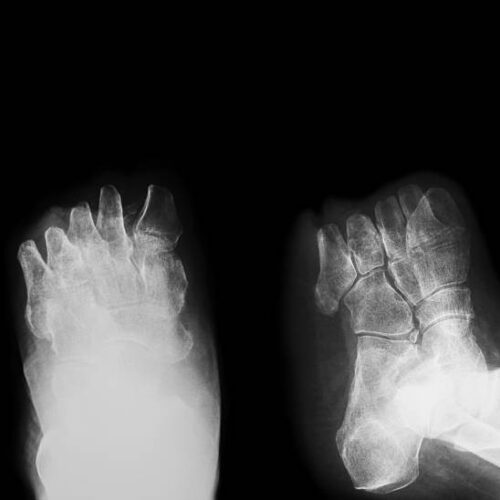

Вальгусна деформація стопи — причини, симптоми та способи лікування

Що таке вальгусна деформація стопи, як вона виникає, які симптоми можуть насторожити, та які методи лікування найефективніші